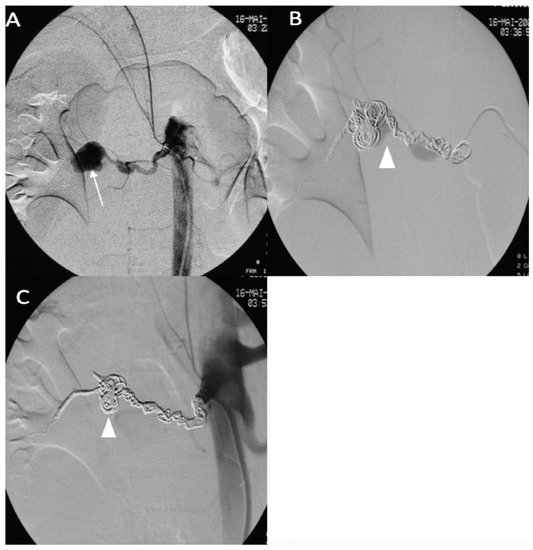

A 25-year-old male patient, with a familial history aortic rupture leading to the sudden death of his father in 1999, was referred to our hospital after the appearance of a left groin hematoma. An enhanced abdominal and pelvic CT scan revealed an aneurysm of the splenic artery measuring 30 × 25 mm and a recent dissection of the left common iliac artery, with a maximum iliac diameter of 12 mm (Figure 3A,B). In his medical history, he complained of abdominal pain within the left hypochondrium for the past 8 months following physical exercise. After a multidisciplinary evaluation, we first decided to embolize the splenic aneurysm using coils to prevent the risk of rupture. Under general anesthesia, a 6 F introducer was inserted into the left humeral artery using the Seldinger technique. Two-dimensional/three-dimensional fusion with preoperative CT angiography was performed to guide the catheter and microcatheter for the more rapid catheterization of the aneurysm and to decrease the radiation exposure (Figure 3C). We catheterized the celiac trunk artery using a 6 F ENVOY catheter (Codman-USA) and then catheterized the aneurysm using a Progreat 2.8 F microcatheter (Terumo-Tokyo, Japan). We started to exclude the outflow of the aneurysm with several Ruby coils (Penumbra-Alameda, CA, USA). We then filled the aneurysm with multiple coils starting with a 3D Ruby standard coil of 34 mm diameter and after decreasing the diameter of the coils using interlock detachable coils (IDCs, Boston Scientific, Marlborough, MA, USA), Nester coils (COOK 6 USA), and packing coils (Penumbra-Alameda, CA, USA), and we occluded the aneurysm inflow using Ruby standard coils (Penumbra-Alameda, CA, USA) (Figure 3D).

Figure 3.

(A,B) Abdominal CT angiogram with 3D image and arteriography with image fusion (C,D) showing the aneurysm in the splenic artery (arrows). We marked the proximal and distal extremities of the neck of the aneurysm (head arrow), and then we started the embolization using multiple coils after, within, and before the aneurysm.

Successive CT scan follow-up revealed rapid aneurysmal growth of his left common iliac artery with a 12 mm increase in diameter within one week. The patient complained of left groin pain. A hybrid surgical treatment of left iliofemoral bypass and endovascular exclusion of the internal iliac artery was selected (Figure 4).

Figure 4.

(A) Abdominal CT angiogram with 3D image showing the dissection of the left common iliac artery (arrow); (B) arteriography shows the left iliofemoral bypass (star) and dissection of the left common iliac artery (arrow); (C) occlusion of the left internal and external iliac arteries by coils and then a plug (head arrow); (D) arteriography final shows the permeability of left iliofemoral bypass (star).